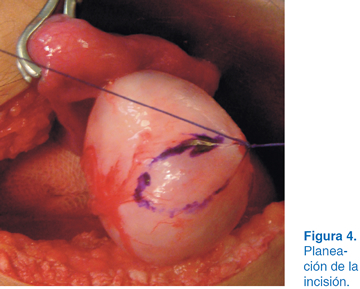

A los dos años del evento quirúrgico en el USG se apreció una tumoración en el ovario izquierdo con dimensiones de 10 x 12 cm (Figura 1). Se solicitó tomografía axial computarizada (TAC), observándose tumoración con densidades mixtas con diagnóstico probable de teratoma (Figura 2). Se optó por laparotomía exploradora donde se identificó el útero y se apreció tumoración dependiente de ovario izquierdo (Figura 3). Se realizó planeación de incisión (Figura 4), posteriormente tumorectomía (Figura 5) y salvamento de tejido ovárico (Figura 6). El reporte transoperatorio mostró teratoma monofásico con bordes libres de tumor.